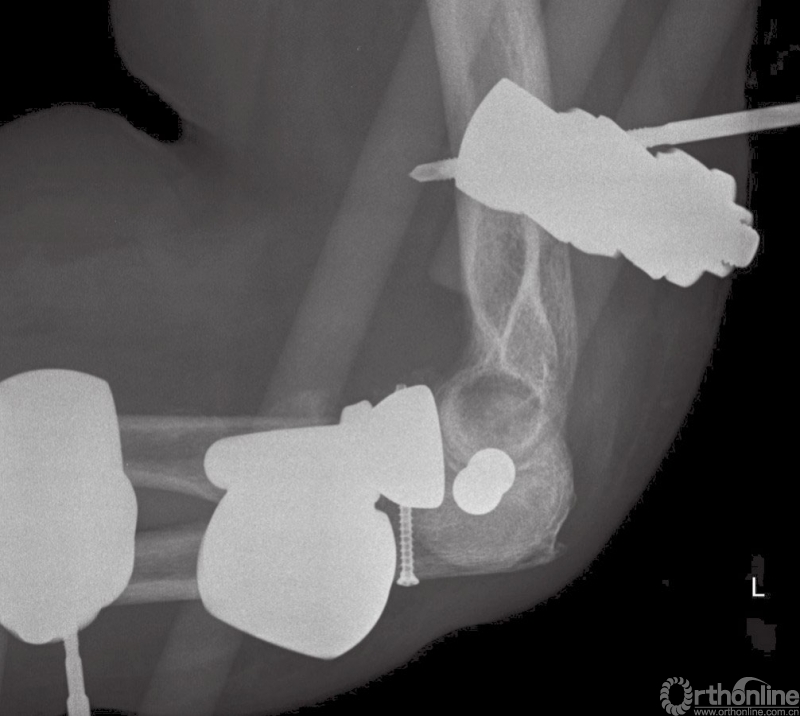

图8 (与图2为同一患者)使用铰链式外固定支具后的术后正位X线片

图9 (与图2为同一患者)使用铰链式外固定支架后的术后侧位X线片